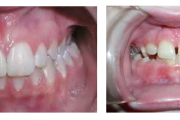

Puudub ülemine tsentraalne intsisiiv, kuid külgmised lõikehambad on juba lõikunud.

Turritavad ülemised lõikehambad.

Puudub ülemine tsentraalne intsisiiv